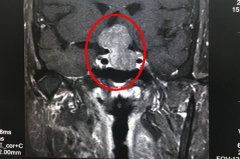

青海年轻妈妈求医两年 李士其专家团队经鼻蝶窦入路为其切除垂体瘤

脑科专家 | 锁孔入路微创手术 鞍区“地雷”一朝切除

垂体柄囊肿,会压迫临近的脑神经、垂体、视神经,引起头晕头痛、内分泌功能紊乱、视力障碍等,犹如患者颅内被安置了一枚地雷。如何用有效、安全,又能减轻患者痛苦的手术方法为患者排除这枚地雷,直接考验...【详细】